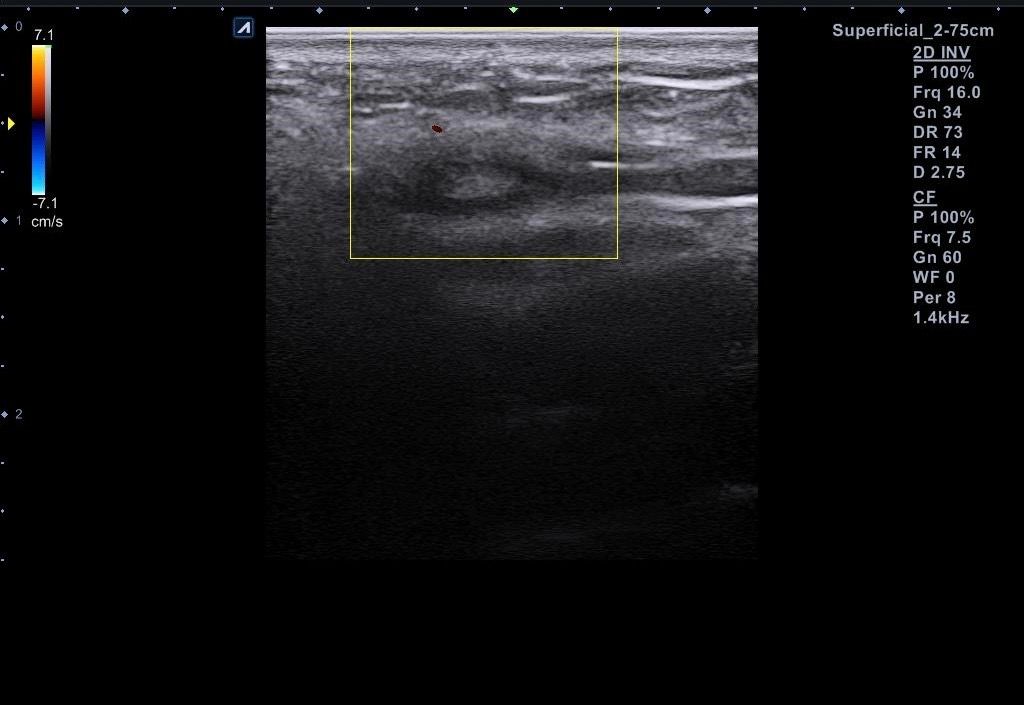

근데 병원에서 지방종이 아니라 임파선 같다고 일단 초음파 본다고 하시고 초음파를 봤는데 의사선생님이 귀 옆에 있는 임파선은 괜찮은데 아래에 있는 임파선이 초음파로 볼때 모양이랑 뭐가 조금 이상하다고 하시면서 대학병원가보라고 소견서를 써주셨습니다 (소견서랑 초음파사진 첨부할게요) 설명들을때 기억상으로는 1 2번째 초음파사진이 귀 아래였던 거 같아요

• 3번 째 사진